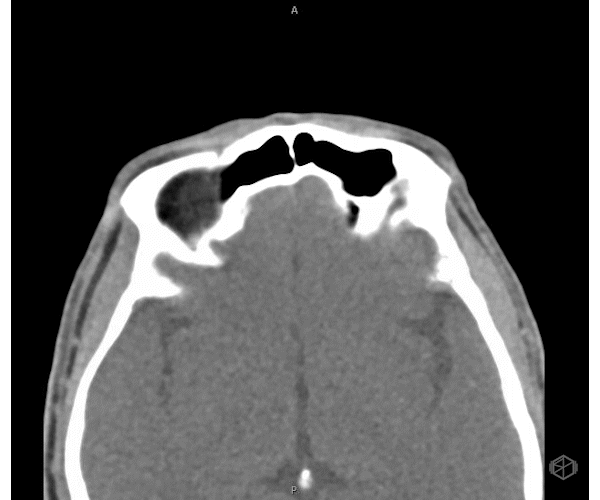

Eye Spy: POCUS Uncovers a Hidden Metallic Foreign Body